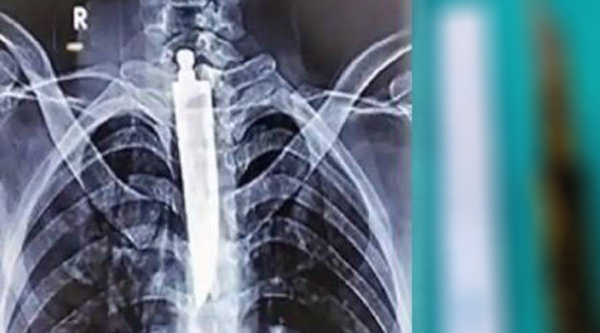

X-ரேயில்……..

அவரது கழுத்து மற்றும் மார்பில் எடுக்கப்பட்ட X-ரேயில், கழுத்து பகுதியில் க.த்.தி மற்றும் ஒரு பேனா refill இருந்தது க.ண்டுபி.டுக்கப்பட்டது. இதனால், அ.தி.ர்.ச்சி.ய.டை.ந்.த மருத்துவக்கு.ழு உ.டனடியாக சி.கி.ச்.சை.யை தொடங்கியுள்ளனர். இதுகுறித்து நோ.யா.ளி.யி.ட.ம் வி.சா.ரி.த்த மருத்துவக்குழு, இரண்டு நாட்களுக்கு முன்பு சமையலறை க.த்.தி.யை வி.ழு.ங்.கி.ய.தா.க கூறியுள்ளார். அவர் வி.ழு.ங்.கிய க.த்.தி சுமார் 14 செ.மீ நீளமும் 3.5 செ.மீ அகலமும் கொண்டுள்ளது என மருத்துவமனை நிர்வாகம் கூறியுள்ளது.